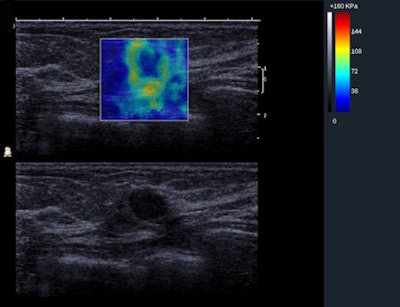

BE1 SWE of a benign mass showing the QBox. This palpable lesion was scored as BI-RADS 4a by the investigator, suggesting it carried a risk of malignancy, but it was soft on SWE with very low Emax values (20 kPa), suggesting that it was benign. Histology of the biopsy specimen revealed a fibroadenoma. Image courtesy of Dr. Christophe Tourasse, Hôpital Louis Mermoz in Lyon, France.Shear-wave elastography is a technique in which an acoustic pressure wave induces slow-moving lateral waves within the tissue, and the speed of propagation of the shear wave is proportional to the square root of the tissue's elastic modulus. Shear waves travel slower in softer tissue and faster in stiffer tissue. Small changes in velocity occur when the waves pass through tissues of varying stiffness, which is then mapped to create an image. SWE features such as the minimum, mean, and maximum elasticity in a region of interest also can be measured.